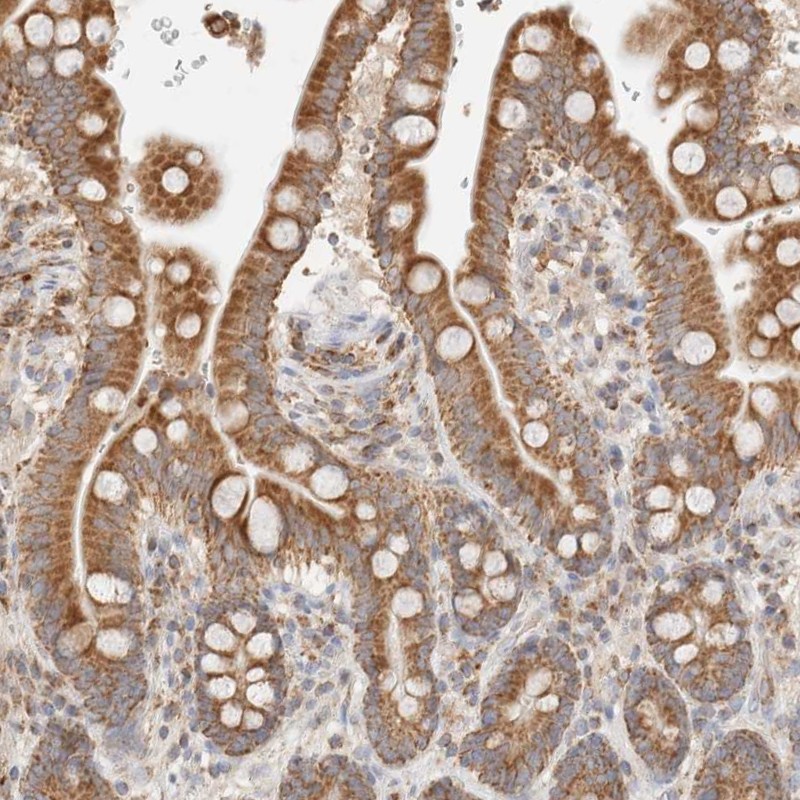

Immunohistochemical staining of human colon shows strong granular cytoplasmic positivity in glandular cells.